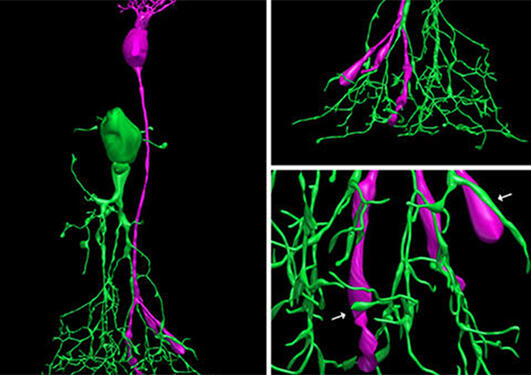

Lundervolds prosjekt vil kobles opp til det nye senteret ved å utvikle og innføre maskinlæringsteknologier som tillater automatisert analyse av medisinske bilder. Maskinlæring, eller mer nøyaktig "dype nevrale nettverk", er teknikker som gjør at datamaskiner kan bidra til å analysere medisinske bilder på samme måte som en trent lege ville - delvis raskere, mer pålitelig og med mye høyere kapasitet. Denne teknikken brukes på bilder som er tatt på moderne medisinsk bildeutstyr, og kommer til å integrere andre data som gensekvenser, kliniske funn og helseregistre. Dette skal føre til at maskinene vil kunne tilby "presisjonsmedisin" for leger og pasienter. Utviklingen av nye metoder i maskinlæring vil spille en viktig rolle i prosjektet. Denne metodologiske forskningen vil bli koordinert av Alexander S. Lundervold, matematiker ved Høyskolen på Vestlandet.

Lundervold påpeker at "vi ønsker ikke å ta ansvar fra legene - men vi ønsker å utvikle teknologi som kan hjelpe og støtte dem". Dette er derfor et svært tverrfaglig prosjekt: mange av de prekliniske og kliniske forskningsgruppene i Bergen samarbeider med Lundervold og hans team. Disse har ulike biomedisinske interesser og pleier å levere bilder fra pasienter, vev eller celleprøver. Datagruppen bruker disse til å utvikle algoritmer, opplære maskiner, og leverer til slutt høykvalitetsanalyse av prøvene. Forskningssamarbeid omfatter aldring og nevrodegenerasjon (Laurence Bindoff, Haris Tzoulis), prostatakreft (CCBIO), livmorkreft (Ingfrid Haldorsen), nyrene (Jarle Rørvik, Olav Tenstad) og hjerne-tarm prosjektet (Trygve Hausken).